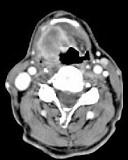

问题 男,63岁,咽喉部不适约1年,近2个月经常咳嗽,痰中带有血丝,CT如图所示,应诊断为()

选项 A.梨状窝癌 B.声门型喉癌 C.声门下型喉癌 D.声门上型喉癌 E.混合型喉癌

答案 D